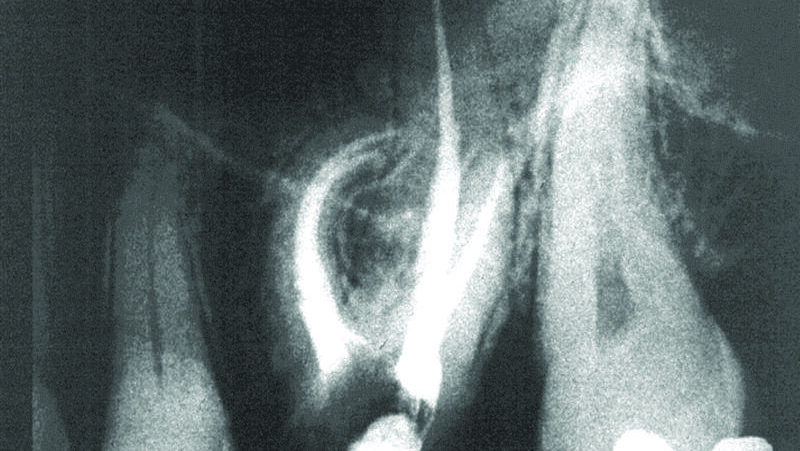

Imajući u vidu smanjenu otpornost NiTi rotirajućih instrumenata na lom sa povećanjem dijametra vrha instrumenta, razumno je smatrati manje preparacije kao adekvatne za obradu i irigaciju kanala. Međutim, ima mnogo dokaza koji ne idu u prilog ovom stavu. Sa praktičnog aspekta, najmanja apikalna preparacija koja omogućava efikasnu irigaciju je ona dimenzija 30, dok je preparacija dimenzija 35 ona koja se preporučuje. Postoje brojne studije u kojima je pokazano da je stepen apikalne preparacije u obrnutoj srazmeri sa brojem bakterija, a smanjen broj bakterija u apikalnom segmentu je usko povezan sa većim uspehom čitavog endodontskog tretmana (Slike 4,5).

Proširivači sa manjim brojem navoja se koriste na način koji omogućava njihovu dugotrajnu upotrebu, praktično eliminišući mogućnost loma instrumenta, dajući stomatologu znatno pouzdanije informacije potrebne za odluku do koje širine treba treba obraditi kanal, sa mogućnošću da se koriste i kao ručni i kao mašinski instrumenti. Njihovo korišćenje na ovaj način nalazi sve veću podršku u stručnoj literaturi u kojoj je dokazano da je moguće postići bolje rezultate u poređenju sa korišćenjem NiTi rotirajućih instrumenata, dok je cena niža za 90%. Zbog toga ne iznenađuje činjenica da ovaj alternativni pristup privlači sve veću pažnju. Klinički slučajevi su prikazani na slikama 5,6 i 7.